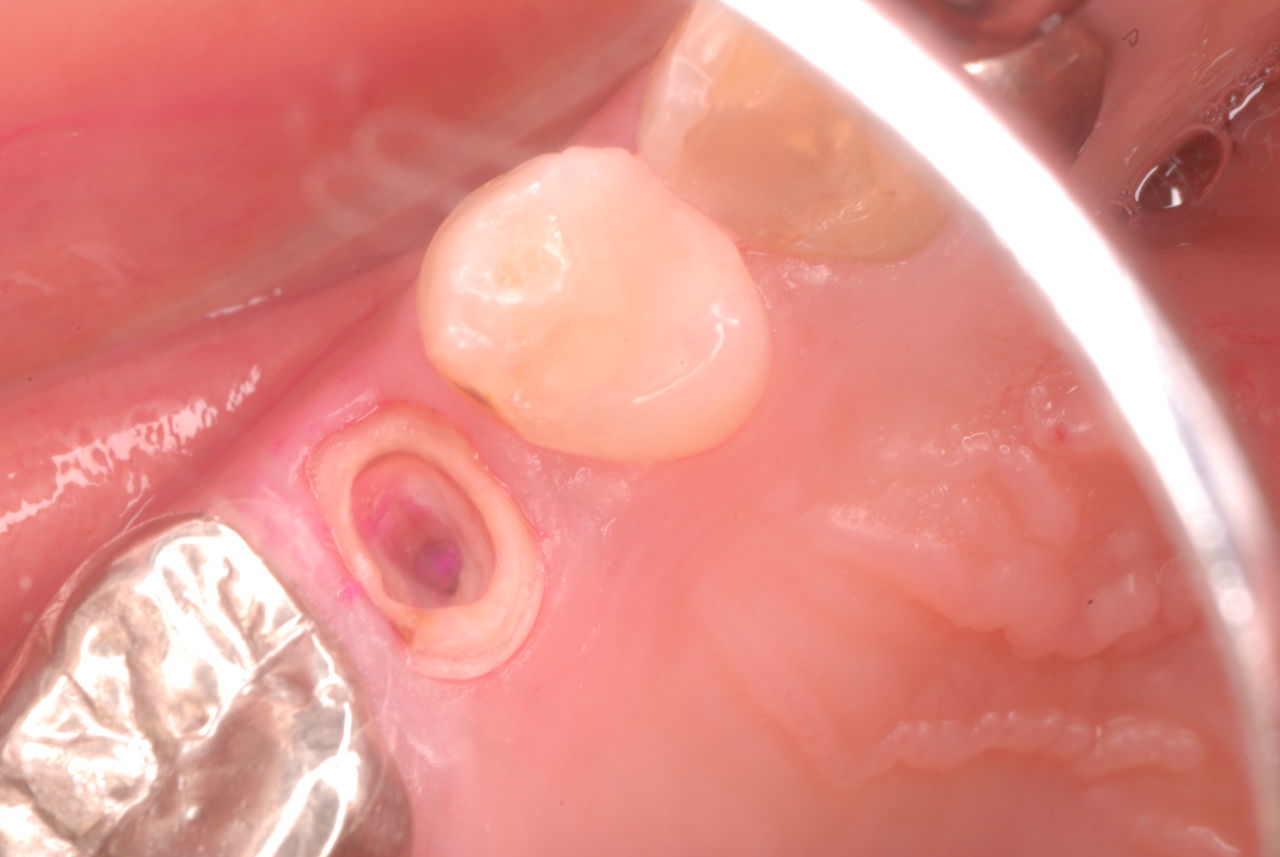

写真左下の親知らずが痛くなり抜歯しました。その後歯茎を除去して虫歯を露出させる処置を二回ほどしています。

レントゲンでは小さいですが、こう言う虫歯が一番怖いのです。

治療の成功率は極めて悪くすぐ再発しやすいのです。